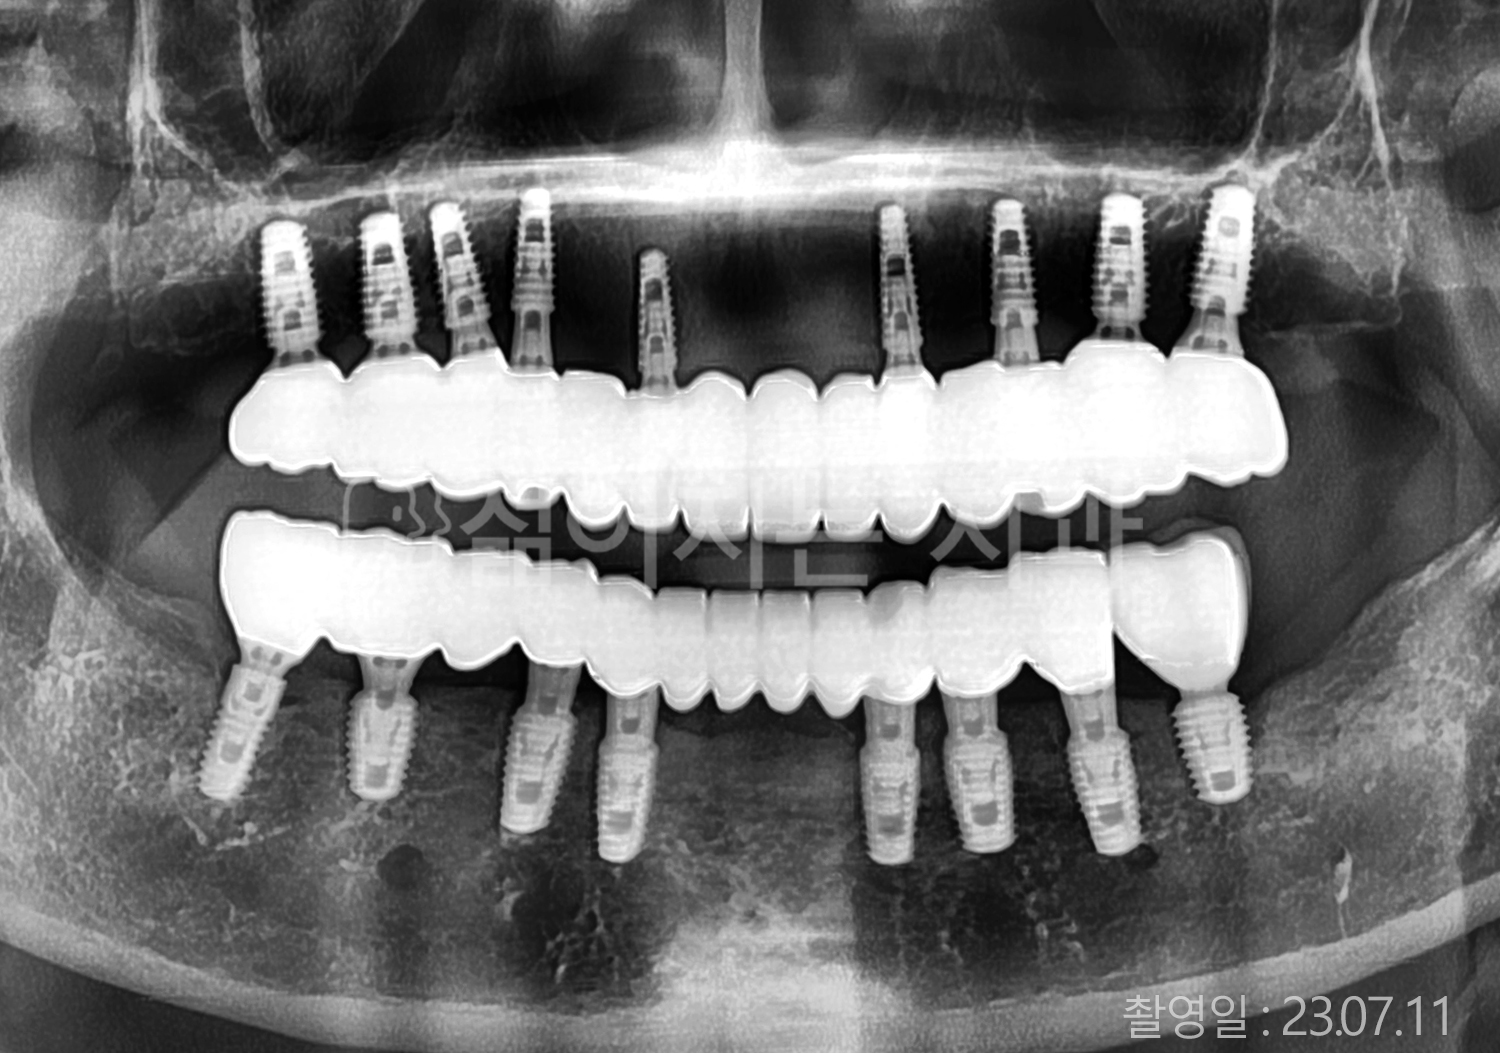

• 70대 고혈압, 고지혈증 전체치아 10개 이상 임플란트

• 60대 당뇨, 간염 전체치아 10개 이상 임플란트

• 80대 골다골증 전체치아 6개 이상 임플란트

• 70대 고혈압, 당뇨 전체치아 10개 이상 임플란트

• 60대 간 질환 전체치아 10개 이상 임플란트

• 60대 전체치아 10개 이상 임플란트

• 70대 전체치아 10개 이상 임플란트

• 50대 전체치아 10개 이상 임플란트

• 60대 고혈압, 고지혈증 전체치아 10개 이상 임플란트

• 40대 고지혈증, 뇌혈관 질환 전체치아 10개 이상 임플란트